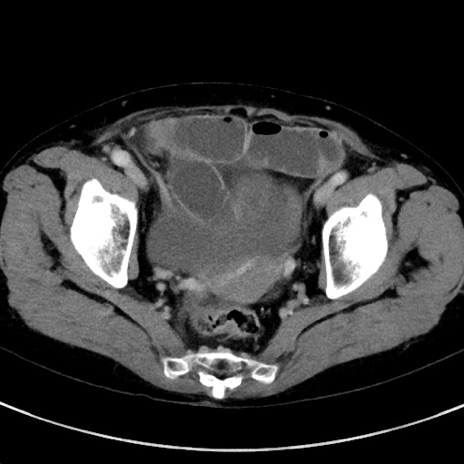

症例23(横断像)

【症例】70歳代女性

【主訴】下腹部痛・嘔吐

【現病歴】2日前より腹痛あり。昨日嘔吐あり。症状改善しないため来院。

【既往歴】胃GISTに対して胃部分切除後。

【身体所見】BT 37.1℃、BP 128/77mmHg、腹部:平坦・軟、下腹部に圧痛あり。

【データ】WBC 10200、CRP 0.31